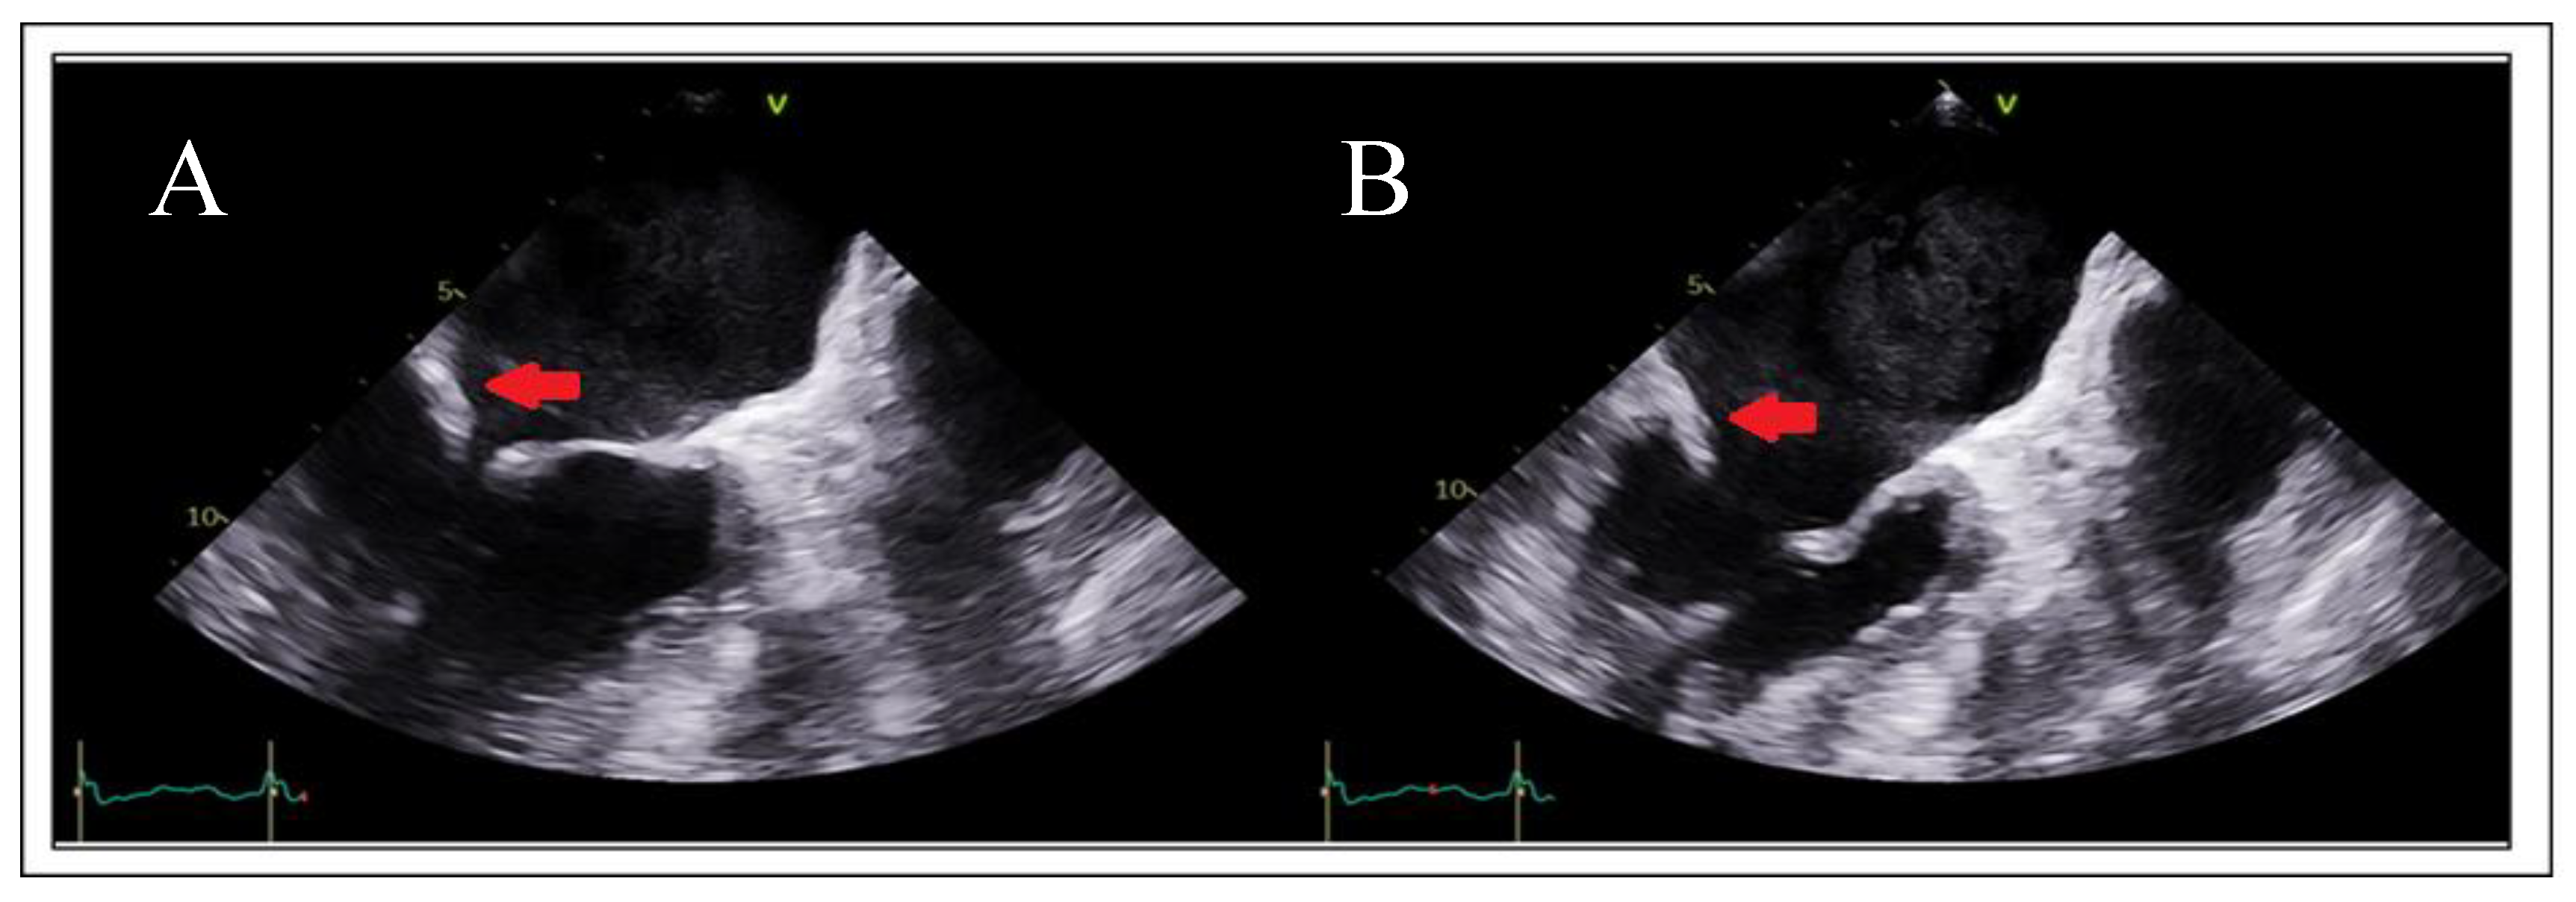

Adequate but Tethered LeafletsPosterior leaflet length may be sufficient, but severe tethering reduces coaptation and grasping success (Figure 11).